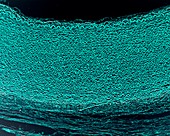

13742424 - Aorta wall, light micrograph